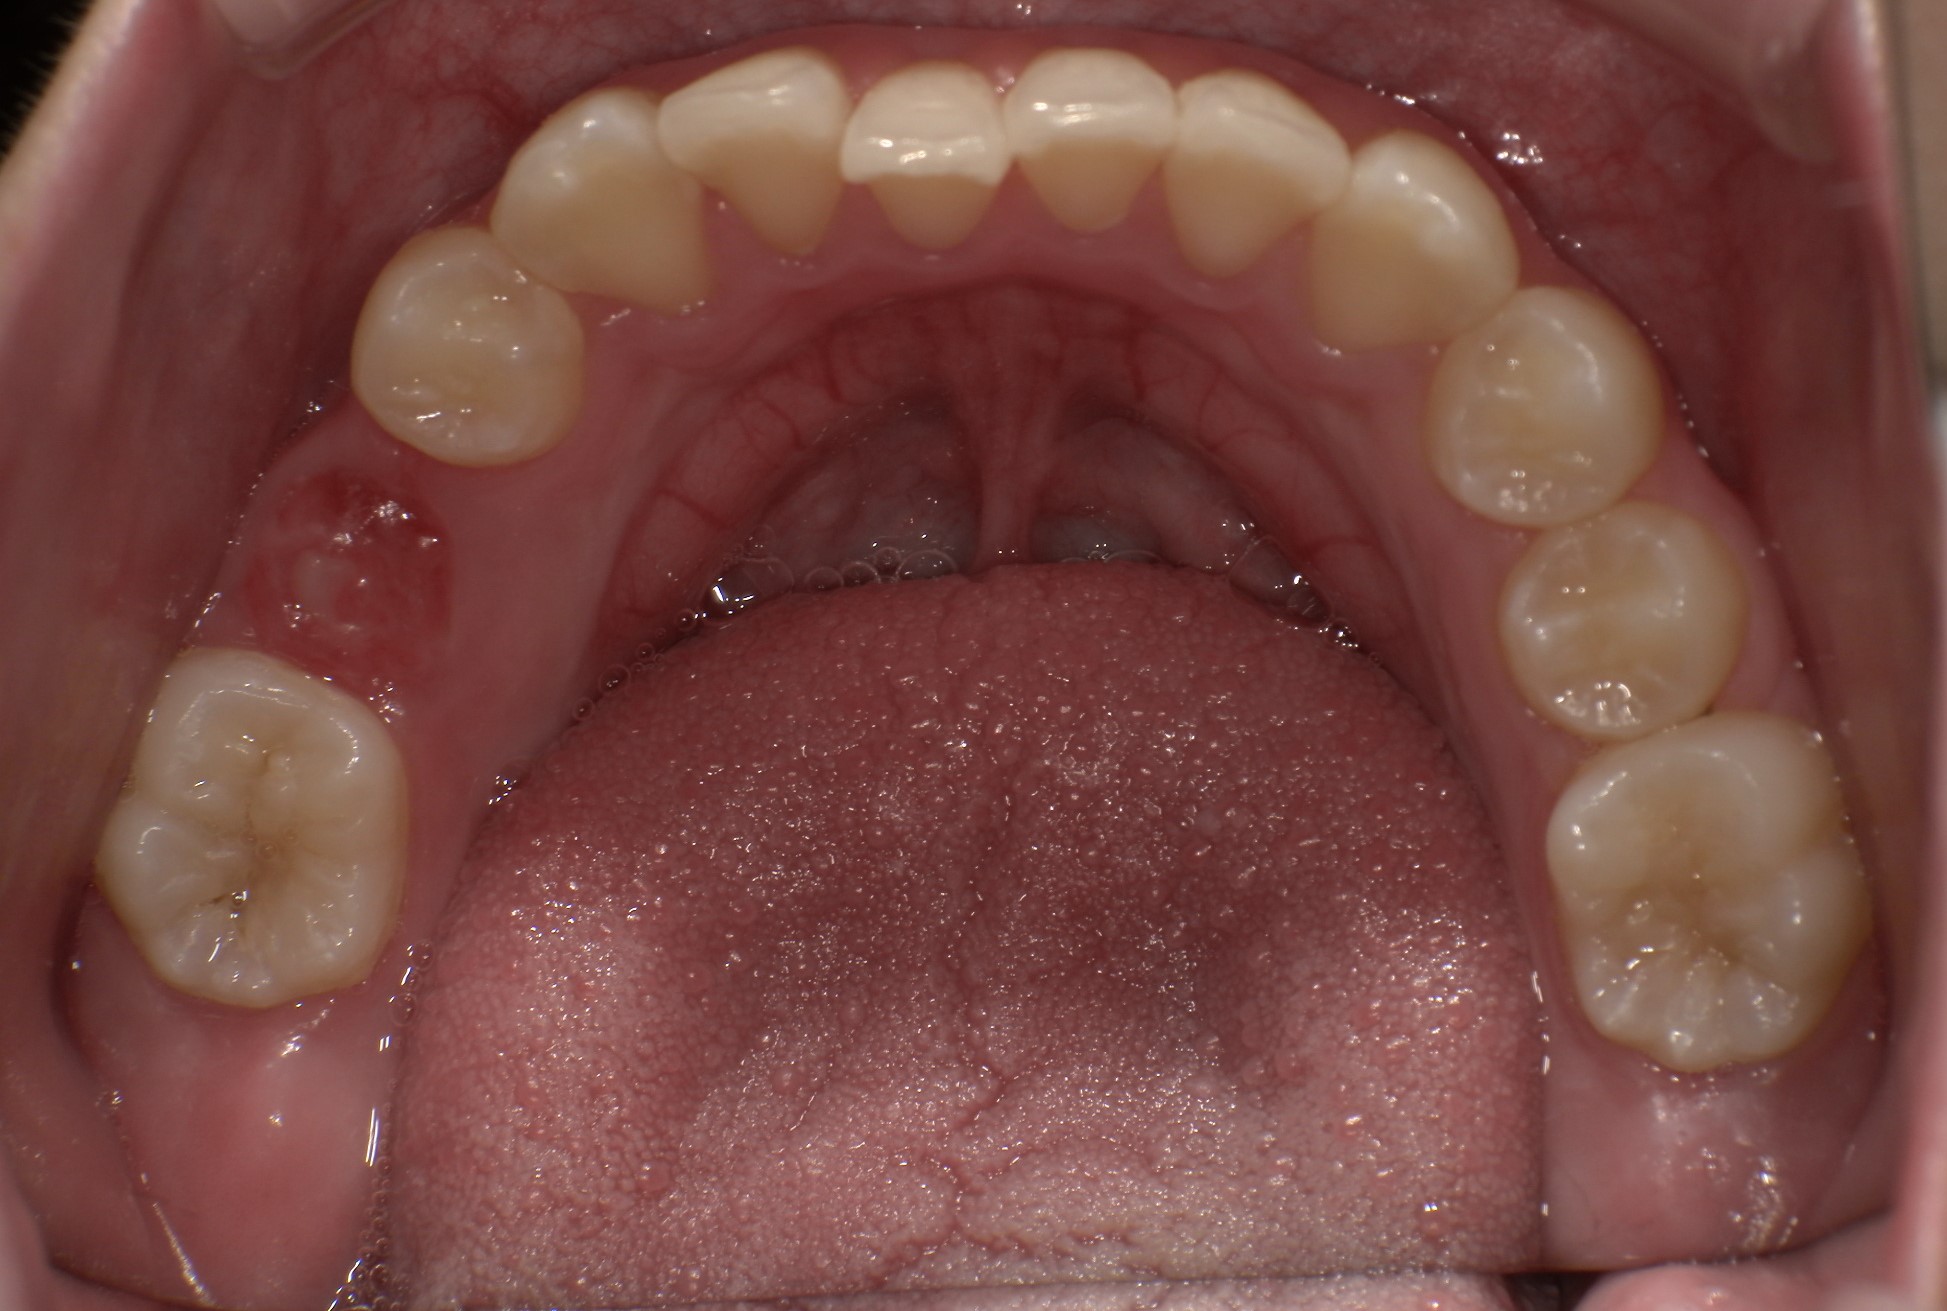

| 年齢・性別 | 8歳11ヶ月の男児 |

|---|---|

| 主訴 | 上顎の永久歯の位置がおかしいとのことで来院。萌出していない右上の前歯の状態に不安を抱えられていました。 |

| 治療期間・回数 | 約3年2ヶ月 |

| 費用 | 440,000円(税別) |